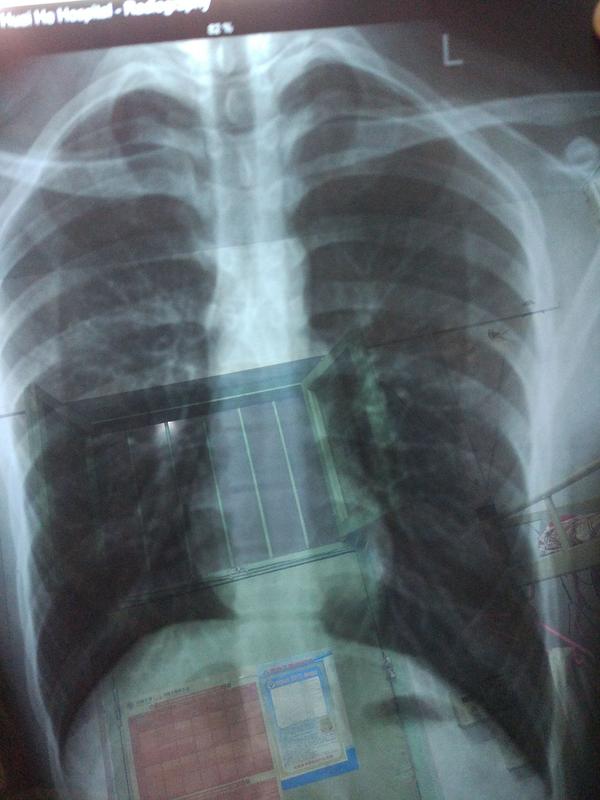

胸片片子,正常的胸片

正常的胸片

正常人胸片

正常肺部胸片

正常胸片

胸片正常图片

健康胸片

正常胸片影像图片